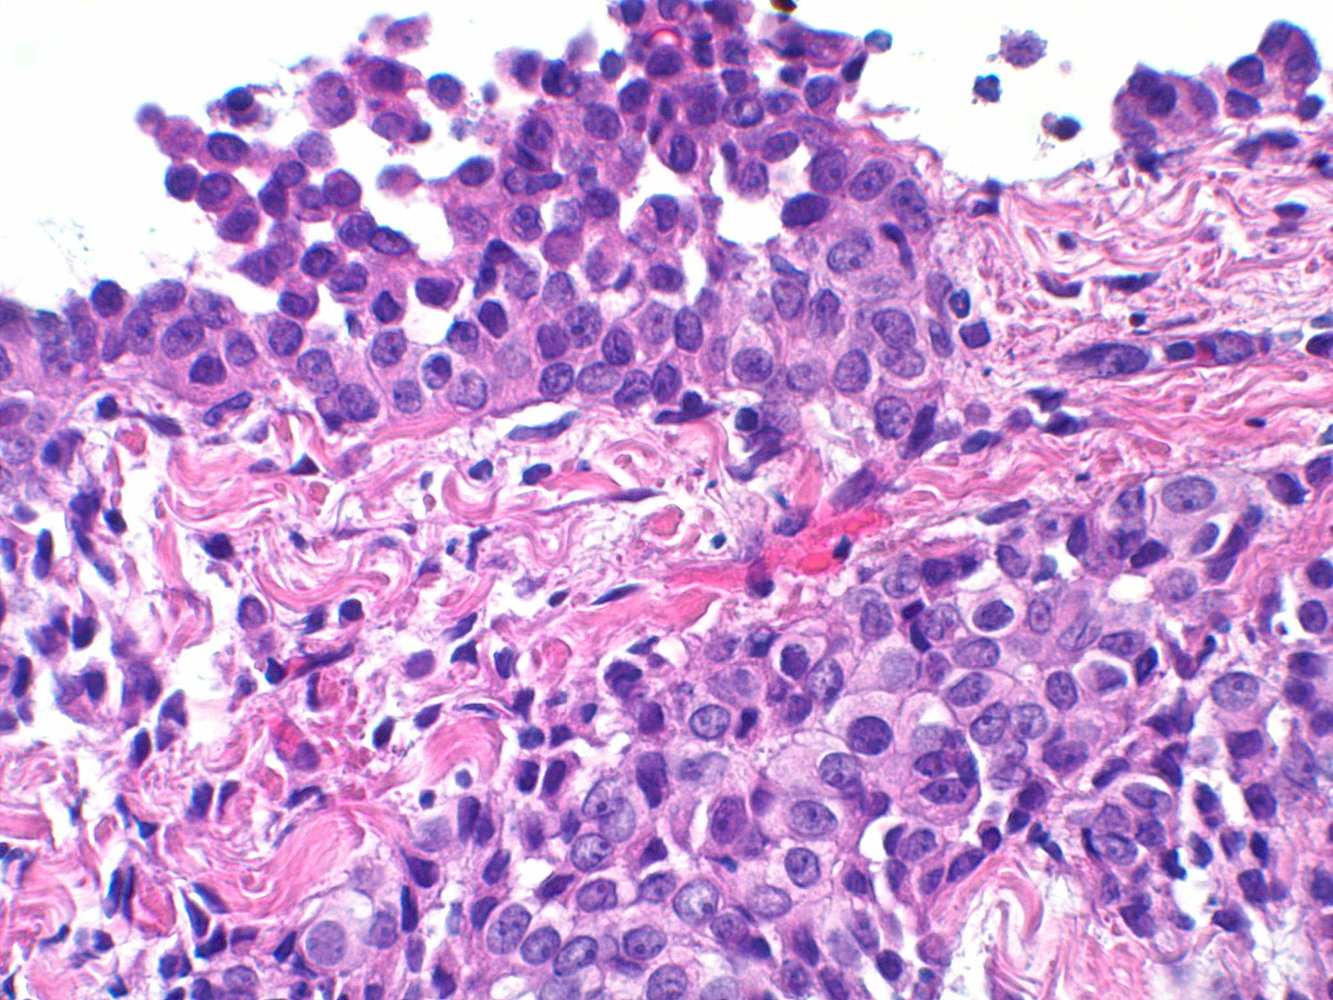

Biopsy

• Uses

• Histopathological confirmation and differentiating mesothelioma from adenocarcinoma

• Confirmation of mesothelioma subtype: epithelioid, sarcomatoid, or mixed

• Modality: usually thoracoscopic biopsy (or laparoscopic biopsy: in suspected peritoneal mesothelioma) [10]

• Findings

• Mesothelioma cells (tumor cells with long and slender microvilli, tonofilaments, and desmosomes on electron microscopy) [12]

• Psammoma bodies (rare, not specific for mesothelioma) [12]

• Immunohistochemical markers: calretinin, cytokeratin 5 and 6, thrombomodulin, and mesothelin [9]

Histopathology is required to confirm the diagnosis of mesothelioma.

In contrast to mesothelioma cells, the tumor cells of adenocarcinomas have short and stubby microvilli and are usually negative for cytokeratin 5 and 6. [12]